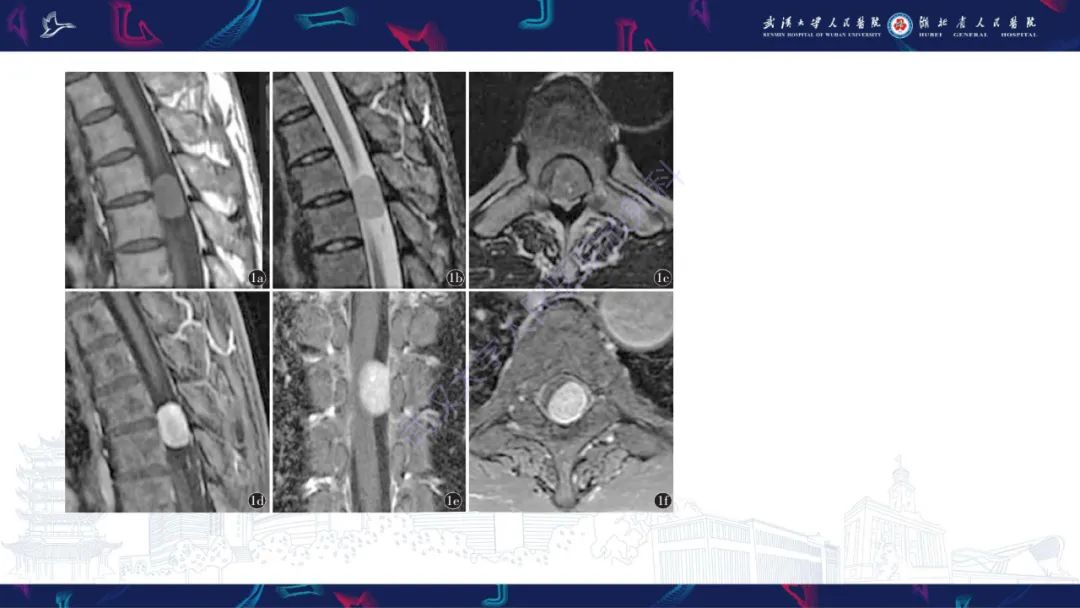

【PPT】椎管内孤立性纤维瘤/血管外皮细胞瘤影像诊断-1